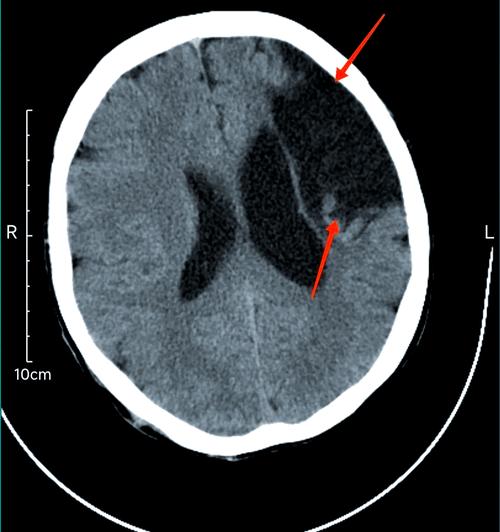

- 影像学表现:在头颅CT或MRI上,急性脑梗在早期(几小时内)可能看不出来,或者仅有轻微的改变,MRI的DWI(弥散加权成像)序列对早期脑梗非常敏感,可以清晰地显示病灶。

- CT:表现为低密度区域,边界清晰,形态不规则,常伴有局部脑沟、脑裂的增宽(脑萎缩)。

- MRI (T1/T2加权像):表现为长T1、长T2信号,即在T1像上比周围脑组织黑,在T2像上比周围白,如果形成囊变,在FLAIR序列上会像一个“黑洞”。

| 影像学 | MRI-DWI高信号,CT早期可能阴性 | CT低密度,MRI长T1长T2信号 |